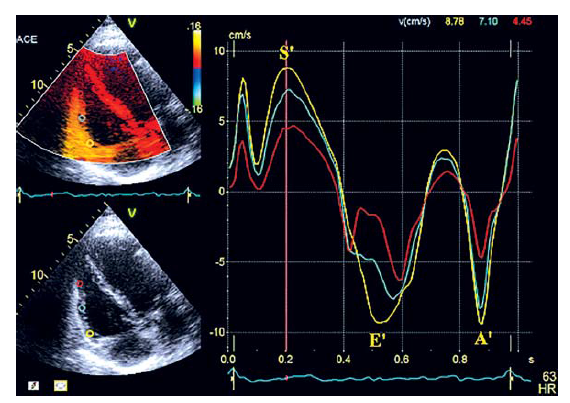

Правосторонний MPI может быть получен двумя способами, с помощью импульсного и тканевого допплеровских режимов (рис. 10 а, б). Использование тканевого допплеровского режима проще, так как все временные интервалы измеряются во время одного сокращения при направлении импульса на латеральную часть трикуспидального кольца. Эта методика доступна для большинства пациентов как с трикуспидальной регургитацией, так и без нее, является легко воспроизводимой, не зависит от ограничений сложной геометрии ПЖ. Одновременно могут быть измерены другие показатели функции правых камер– систолическая скорость экскурсии (S’), скорость раннего диастолического движения (E’) и скорость позднего диастолического движения (A’) на одном изображении. Значения MPI >0,43 для импульсного и >0,54 для тканевого допплеровского режима могут свидетельствовать о дисфункции ПЖ.

Рис. 10. Измерение MPI ПЖ в импульсном допплеровском (а) и в тканевом допплеровском режимах (б)

Для определения S’, контрольный объем помещается на латеральную часть трикуспидального кольца или в центр базального сегмента свободной стенки ПЖ (рис. 12).

Рис. 12. Измерение S’ латеральной части трикуспидального кольца в тканевом допплеровском режиме

По рекомендациям ASE/EACVI (2015) при систолической скорости экскурсии S’ менее 9,5 см/с должно возникнуть подозрение о нарушении функции ПЖ. Показатель систолической скорости экскурсии S’ может быть также получен с помощью цветного допплеровского режима. Пограничное значение этого параметра в соответствии с рекомендациями составило 6 см/с.